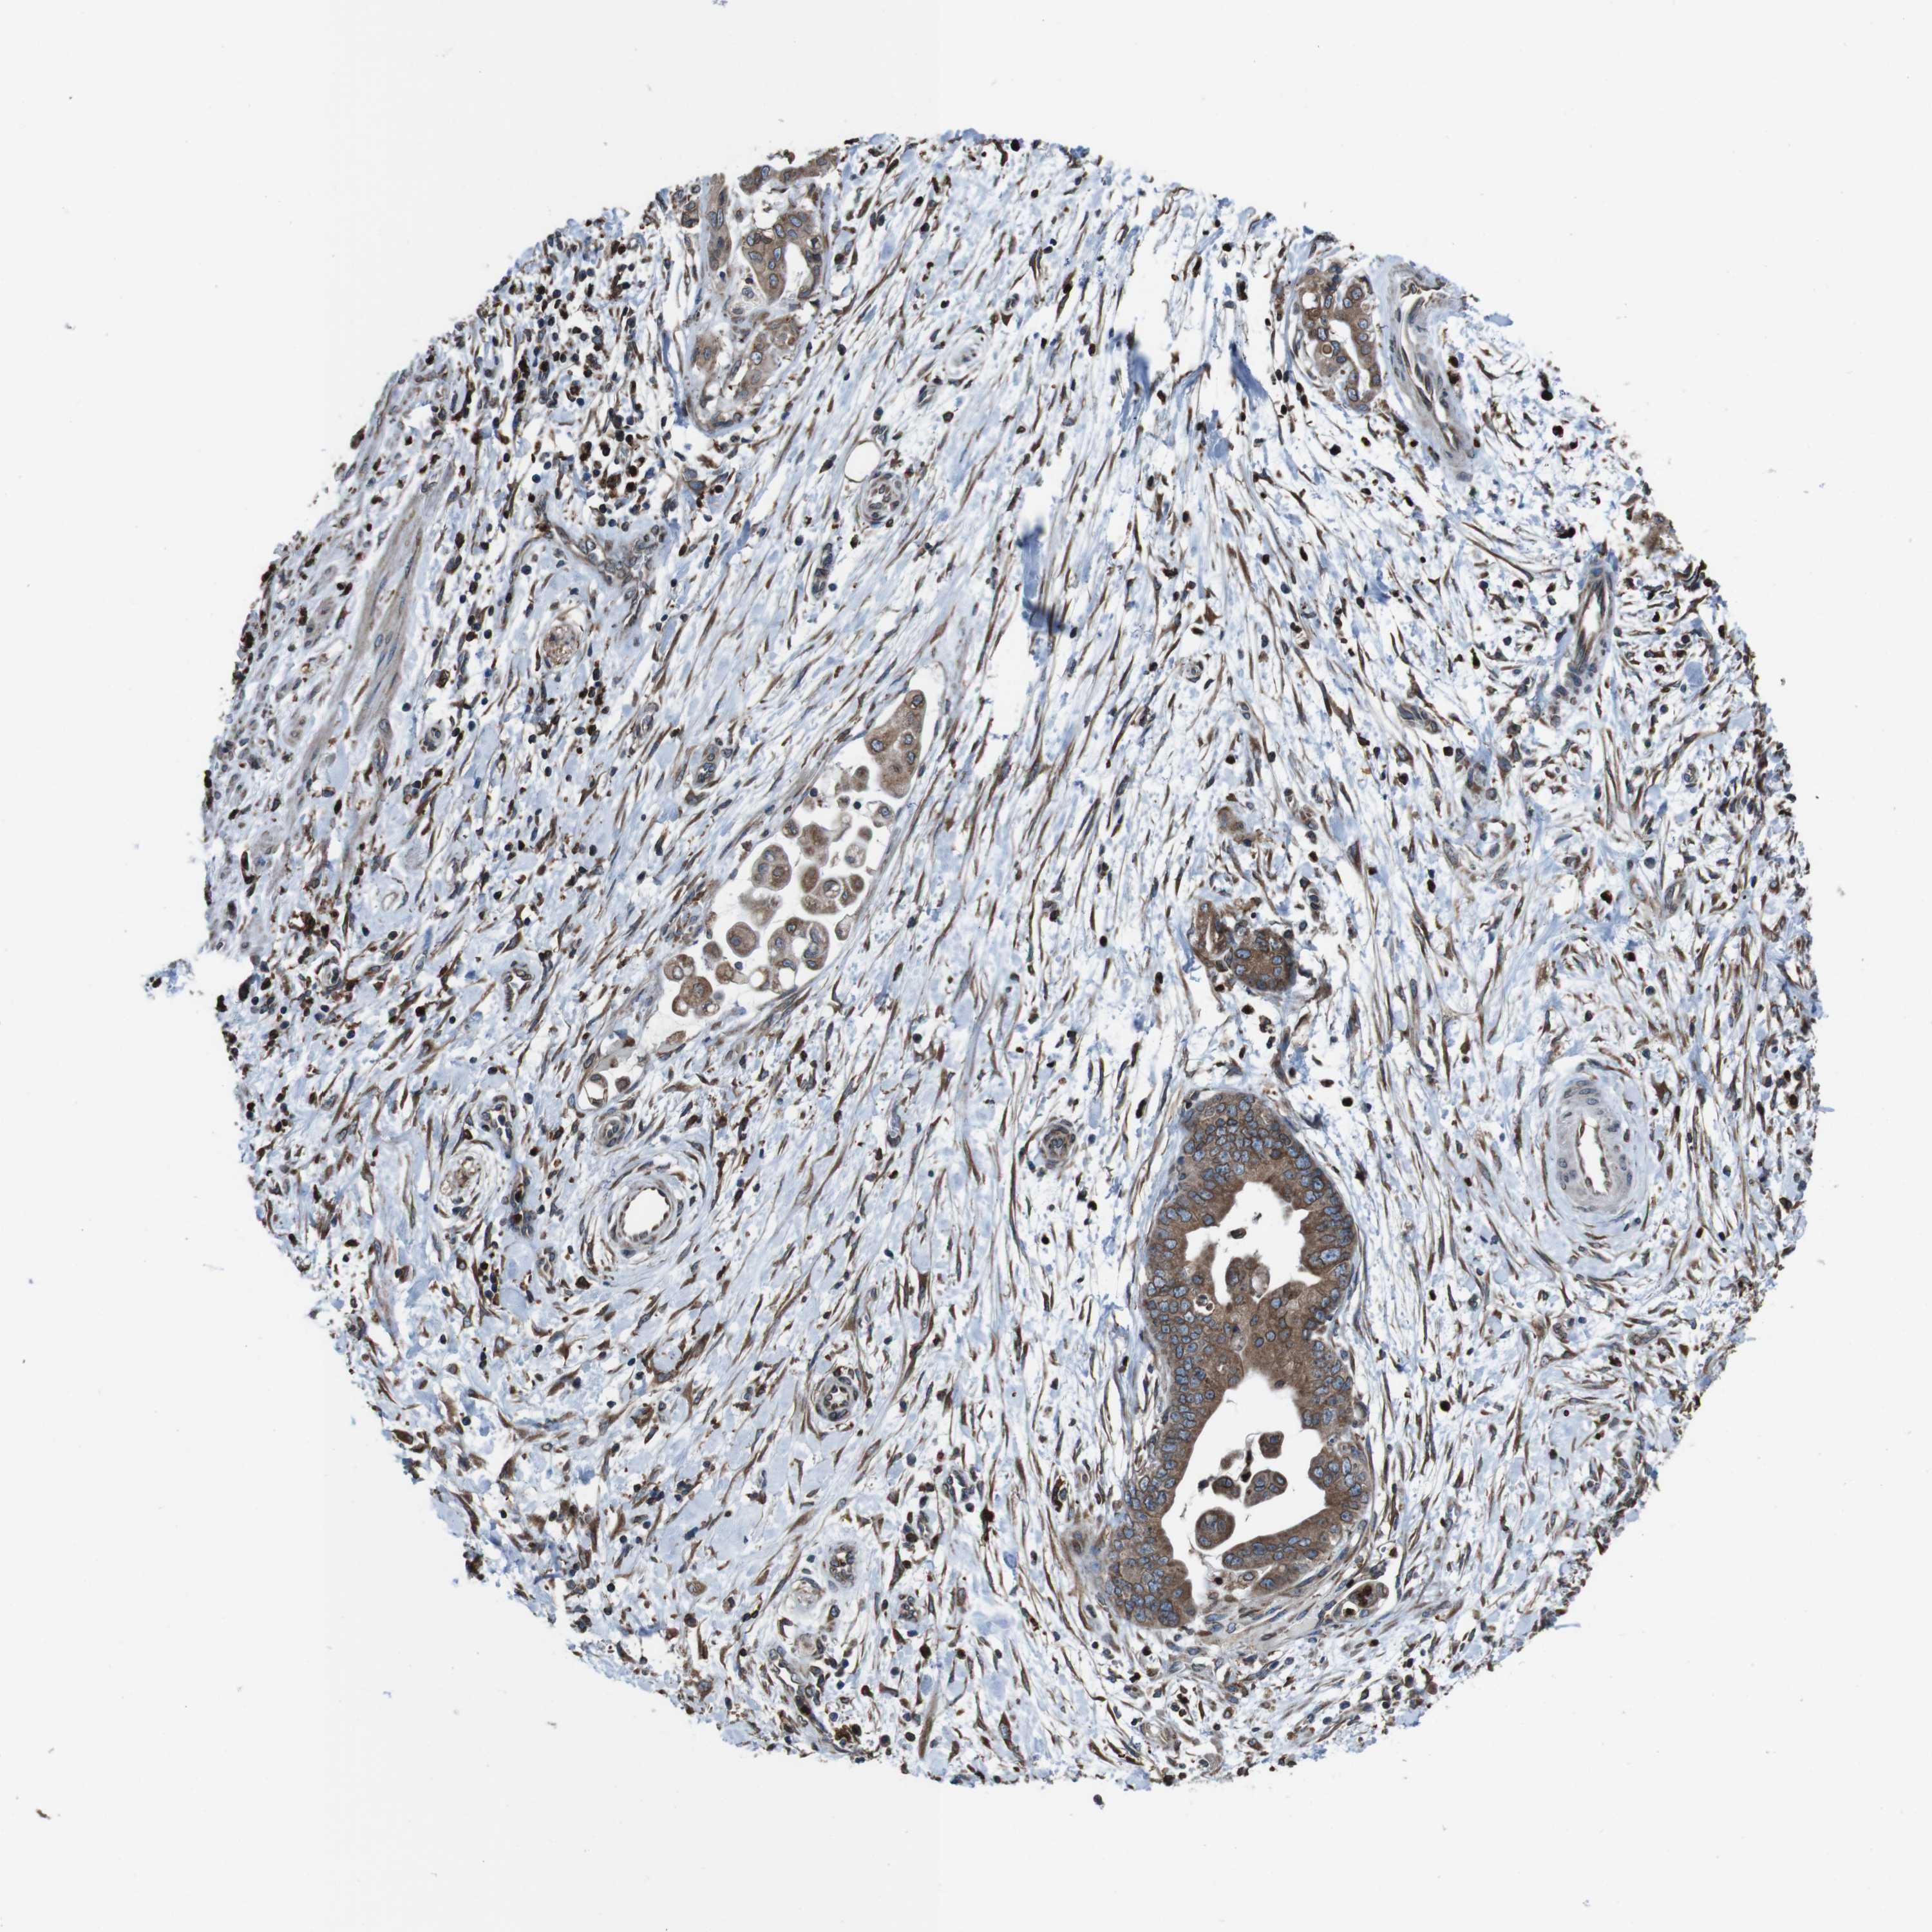

PANCREATIC CANCER - Protein expressioni

A mouse-over function shows sample information and annotation data. Click on an image to view it in a full screen mode. Samples can be filtered based on level of antibody staining by selecting one or several of the following categories: high, medium, low and not detected. The assay and annotation is described here.

Note that samples used for immunohistochemistry by the Human Protein Atlas do not correspond to samples in the TCGA dataset.

Antibody stainingi

Antibody staining in the annotated cell types in the current human tissue is reported as not detected, low, medium, or high, based on conventional immunohistochemistry profiling in selected tissues. This score is based on the combination of the staining intensity and fraction of stained cells.

Each image is clickable and will lead to virtual microscopy that enables deeper exploration of all samples and also displays staining intensity scores, fraction scores and subcellular localization as well as patient and tissue information for each sample.

Antibody HPA012863

Staining

High

Medium

Low

Not detected

Intensity

Strong

Moderate

Weak

Negative

Quantity

>75%

75%-25%

<25%

None

Location

Nuclear

Cytoplasmic/membranous

Cytoplasmic/membranous,nuclear

Adenocarcinoma, NOS